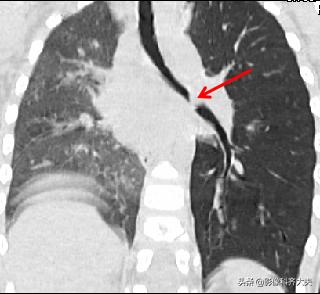

病例6、病史:女,两岁,吃花生时喝水引起呛咳。

轴位显示左侧支气管疑似异物,红色箭头。

冠状位重建清晰显示左侧支气管异物,红色箭头所示。

最小密度投影显示的更加清楚。

这是CPR(曲面重建),即单独对左侧支气管进行重建显影,清晰显示异物。

曲面重建后在进行最小密度投影重建,异物显示的更加清晰。